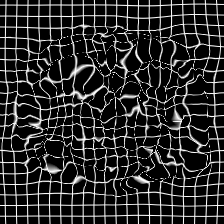

In clinical practice, well-aligned multi-modal images, such as Magnetic Resonance (MR) and Computed Tomography (CT), together can provide complementary information for image-guided therapies. Multi-modal image registration is essential for the accurate alignment of these multi-modal images. However, it remains a very challenging task due to complicated and unknown spatial correspondence between different modalities. In this paper, we propose a novel translation-based unsupervised deformable image registration approach to convert the multi-modal registration problem to a mono-modal one. Specifically, our approach incorporates a discriminator-free translation network to facilitate the training of the registration network and a patchwise contrastive loss to encourage the translation network to preserve object shapes. Furthermore, we propose to replace an adversarial loss, that is widely used in previous multi-modal image registration methods, with a pixel loss in order to integrate the output of translation into the target modality. This leads to an unsupervised method requiring no ground-truth deformation or pairs of aligned images for training. We evaluate four variants of our approach on the public Learn2Reg 2021 datasets \cite{hering2021learn2reg}. The experimental results demonstrate that the proposed architecture achieves state-of-the-art performance. Our code is available at https://github.com/heyblackC/DFMIR.

图像配准是图像处理研究领域中的一个典型问题和技术难点,其目的在于比较或融合针对同一对象在不同条件下获取的图像,例如图像会来自不同的采集设备,取自不同的时间,不同的拍摄视角等等,有时也需要用到针对不同对象的图像配准问题。具体地说,对于一组图像数据集中的两幅图像,通过寻找一种空间变换把一幅图像映射到另一幅图像,使得两图中对应于空间同一位置的点一一对应起来,从而达到信息融合的目的。 该技术在计算机视觉、医学图像处理以及材料力学等领域都具有广泛的应用。根据具体应用的不同,有的侧重于通过变换结果融合两幅图像,有的侧重于研究变换本身以获得对象的一些力学属性。